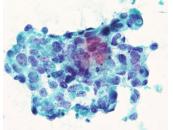

第40回日本臨床細胞学会九州連合会学会(大分)スライドカンファレンス症例1

種別:婦人科

出題:橋口 真理子 佐賀大学医学部病因病態科学講座

| 年齢 | 10代 | 性別 | 女性 |

| 採取部位 | 右卵巣腫瘍 | 採取方法 | 捺印細胞診 |

現病歴 手術の2か月前頃から腹部膨満感を自覚し近医受診。腹部エコーで骨盤内に17㎝大の充実性腫瘤を指摘され当院受診。右側卵巣腫瘍の診断で手術が施行された。右付属器切除術が行われ、術中迅速に提出された。右卵巣は20㎝程度に腫大し、割面は黄白色調で充実性腫瘤であった。捺印細胞診を採取した。

術前の採血では、hCG329mIU/ml (1.0 以下)、AFP3.3ng/ml(0~7.0)、CA125 92 U/ml (0-35)、LDH 2772U/L (124-222)であった。

| 正解 | 2.Dysgerminoma |

▼選択肢及び投票結果

| 1.Yolk sac tumor | 17件 | (16.2%) | |

| 2.Dysgerminoma | 77件 | (73.3%) | |

| 3.Granulosa cell tumor | 2件 | (1.9%) | |

| 4.Clear cell carcinoma | 7件 | (6.7%) | |

| 5.Neuroendocrine carcinoma | 2件 | (1.9%) | |

| 投票総数 | 105件 | (100%) |